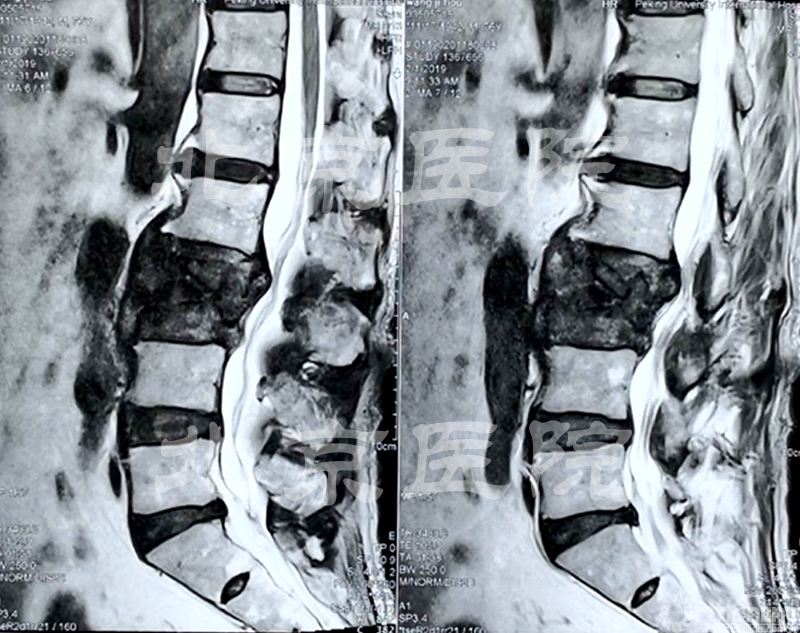

术前MRI及MRM检查

患者为75岁女性。在2000年出现腰痛,伴左下肢放射痛,间歇性跛行300米,保守治疗后症状有所缓解;2002年下肢痛加重,CT、MRI提示L3/4、L4/5、L5/S1椎间盘突出,椎管狭窄,于2002年11月第一次入院手术,行腰椎长阶段固定融合术治疗。